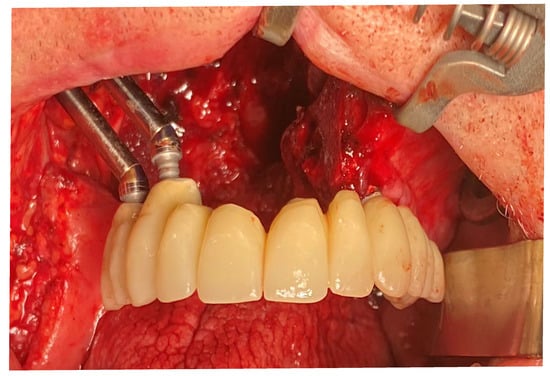

Multi-unit abutments (MUA) and provisional titanium abutments were placed accordingly with the digital project. The provisional prosthesis also served for checking the precision of the intervention performed. After verification, the provisional prosthesis was connected to the titanium provisional abutment that was screwed onto the zygomatic implants (Figure 14).

Figure 14.

Full-arch upper provisional in place.